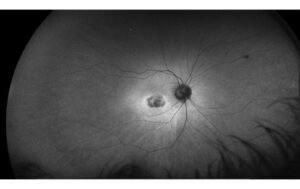

Myopia occurs when the eyeball is too long or the cornea or lens is too curved, which causes light to focus in front of the retina instead of on it. This causes distant objects to appear blurry while nearby objects appear clear. Environmental factors such as spending too much time indoors or doing close-up work, such as reading, writing, or using electronic devices, can increase the risk of developing myopia.

Myopia occurs when the eyeball is too long, causing light to focus in front of the retina instead of on it. This results in distant objects appearing blurry while nearby objects remain clear. However, what causes the eyeball to elongate in the first place? Genetics play a significant role in myopia development, and myopic parents’ children are more likely to develop the condition.